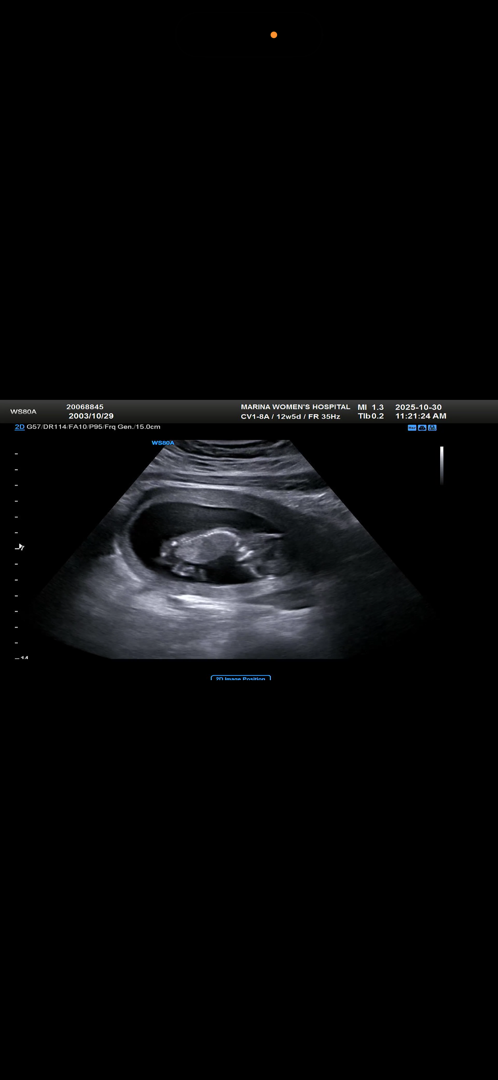

12주5일 초음파 봐주세용!

친구들은 남자 아이 같다는데 다른 분들은 어떤지 궁금해요!!